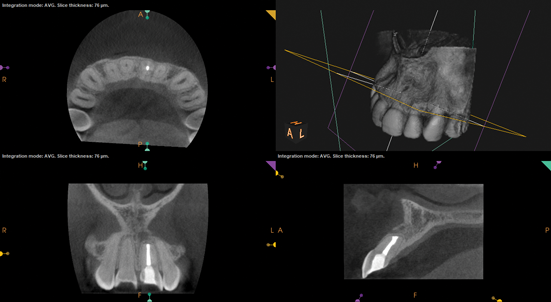

(9.) Preoperative radiograph of previously treated tooth No. 9, which received a diagnosis of acute apical abscess secondary to childhood trauma and recurrent endodontic pathology.

Figure 9

(10.) Posttreatment radiograph and cone-beam computed tomography (CBCT) scan following nonsurgical root canal re-treatment that resulted in incomplete resolution of symptoms in response to percussion and palpation.

Figure 10

(11.) Posttreatment radiograph and cone-beam computed tomography (CBCT) scan following nonsurgical root canal re-treatment that resulted in incomplete resolution of symptoms in response to percussion and palpation.

Figure 11

(12.) Postoperative radiograph after apical surgery was performed using MTA as an apical retrofilling material.

Figure 12

(13.) Normal healing was noted clinically and radiographically at the 6-month follow-up appointment.

Figure 13